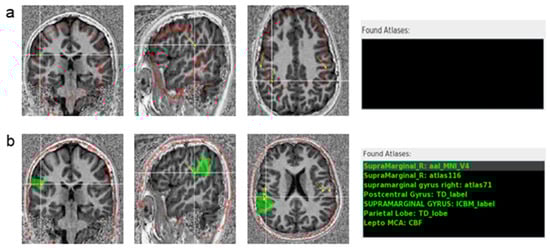

3.1. Usage of the Program Tools